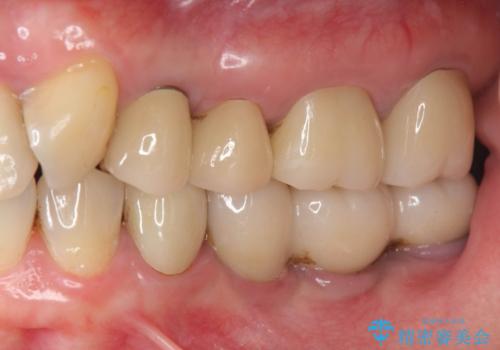

[ 歯ぐきから出血をする ] 歯周外科を伴うセラミックやりかえ治療

![[ 歯ぐきから出血をする ] 歯周外科を伴うセラミックやりかえ治療の症例 治療前](https://seimitsushinbi.jp/wp/wp-content/uploads/2024/12/dad9bd6fd8fdc9454170eb3e86a080a9-500x350.jpg?v=1733474741)

![[ 歯ぐきから出血をする ] 歯周外科を伴うセラミックやりかえ治療の症例 治療後](https://seimitsushinbi.jp/wp/wp-content/uploads/2024/12/39b2ace77ddc630ec8fbb92d0a9c107d-500x350.jpg?v=1733474802)